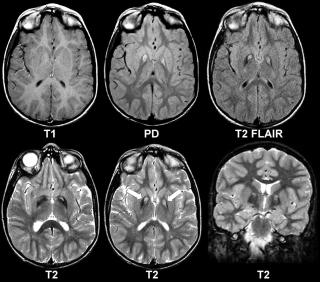

Что покажут снимки МРТ

- Нарушение диастолической функции

- Участки усиления с негомогенной высокой Т2-интенсивностью сигнала

- Перикардиальный и плевральный выпот

- Возможно поражение легких.